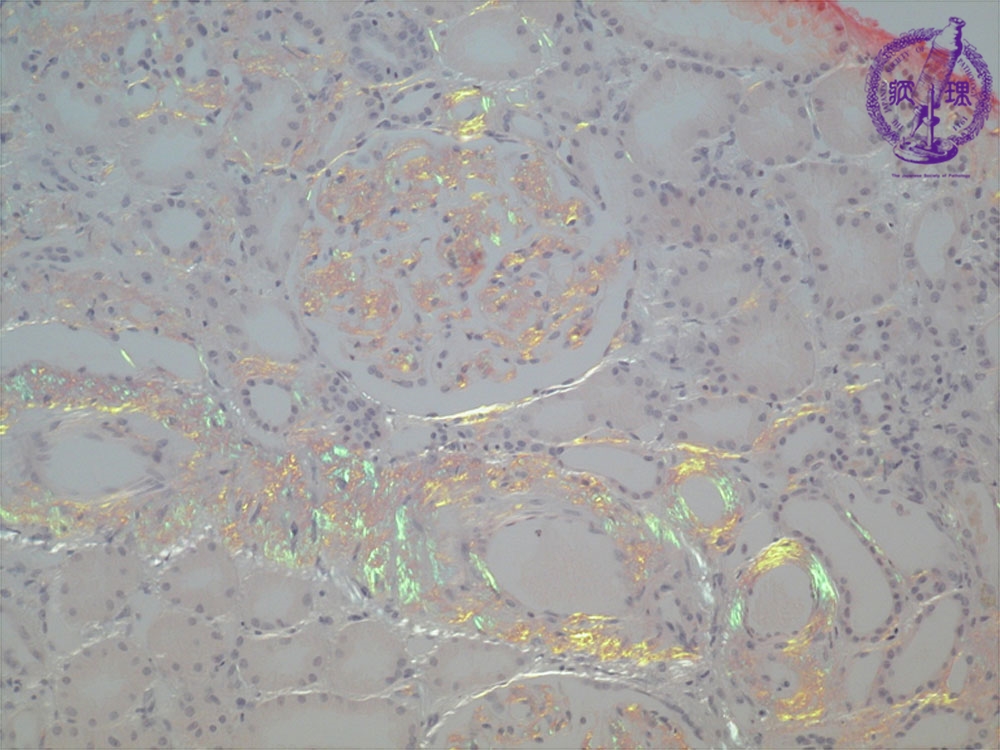

Microscopic findings ( Congo red, middle power view): Amyloid reveals apple green birefringence under polarized light.